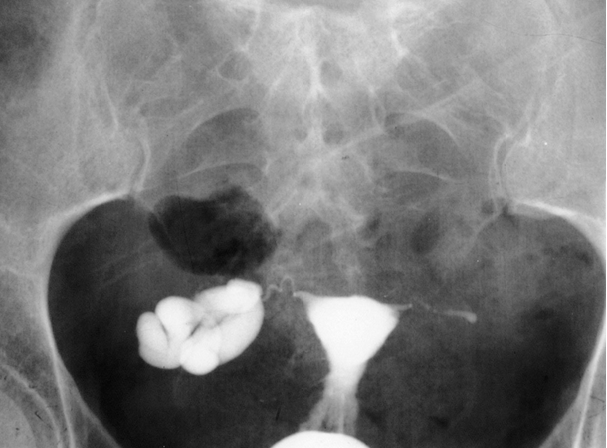

Tuberculose génitale femelle.png